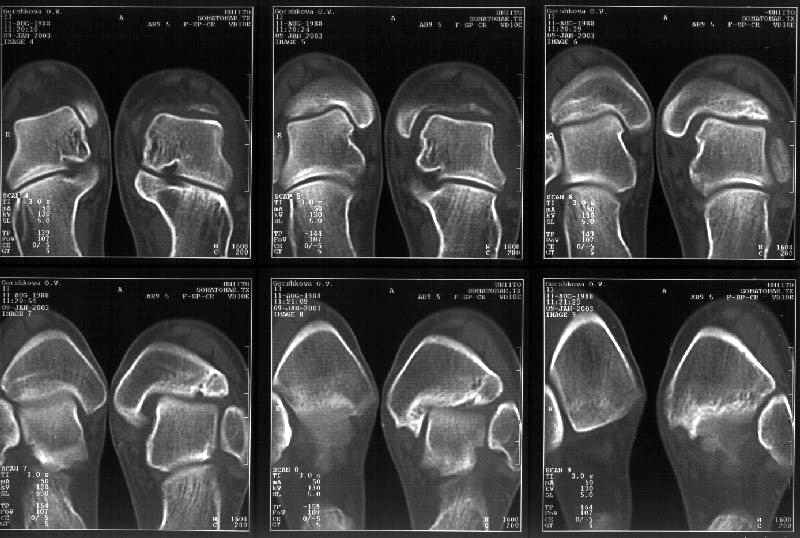

Отправитель: Alexander Chelnokov 19 Январь 2003, 22:34

Сегодня пациентке сделали сравнительную КТ. А ксиальные и Фронтальные срезы приложены. Ваше мнение?

Фронтальные

Аксиальные

Отправитель: Й. Воск 19 Январь 2003, 22:37

Спасибо за КТ -она изумительная. К сожалению, я по дороге на врачебный викенд на Мёртвом море и не смогу подготовить комментарий и схемку до 19.01.03 Помоему, результат КТ даёт чёткую возможность красивой и эффективной помощи.

Отправитель: Й. Воск 19 Январь 2003, 22:50

На КТ я попытался изобразить скромными своими способностями (А)- место перелома, (С)- нормальный суставной зазор меж тараном и тремя его маллеолами. (В)- образовавшийся в результате перелома широкий раза в три зазор, позволяющий, по-моему, сублюксацию тарана при ходьбе. В свете данных КТ, критически важных, я бы предложил вертикальную остеотомию места перелома

задне-внутренним подходом и фиксацию мед. маллеола прижатым к тарану с помощью тонкого compression screw. После этого гипсовый сапожок и немедленное расхаживание ноги.